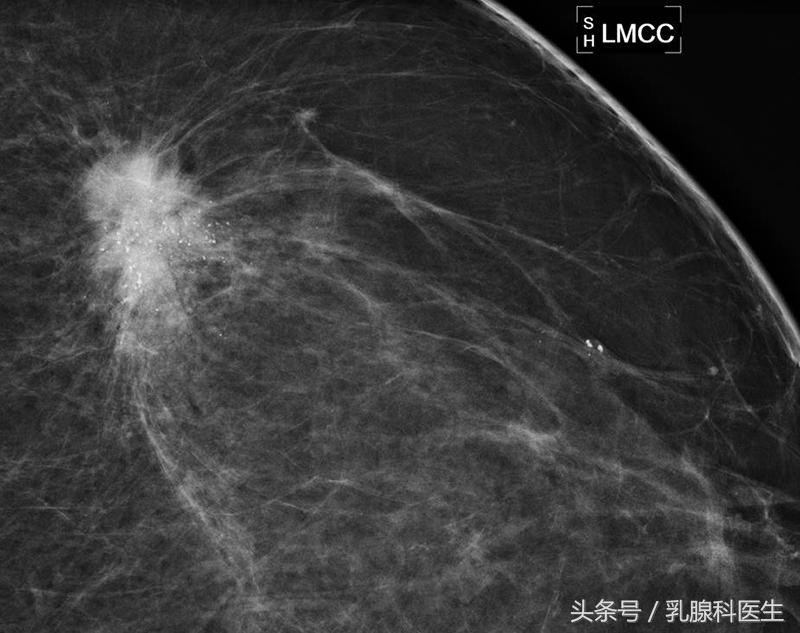

BI-RADS 5:高度怀疑恶性(几乎肯定的恶性),临床应采取适当措施。这一类病变的恶性可能性大于等于95%。

目前认为,适当的腹部隔离防护下,乳腺钼靶是被允许!乳腺钼靶的辐射剂量远远低于研究表明的可能会增加胎儿先天畸形和发育迟缓的的辐射剂量!乳腺核磁共振用于妊娠期和哺乳期女性乳腺诊断的前瞻性研究!也没有钆应用与妊娠期的安全性数据!